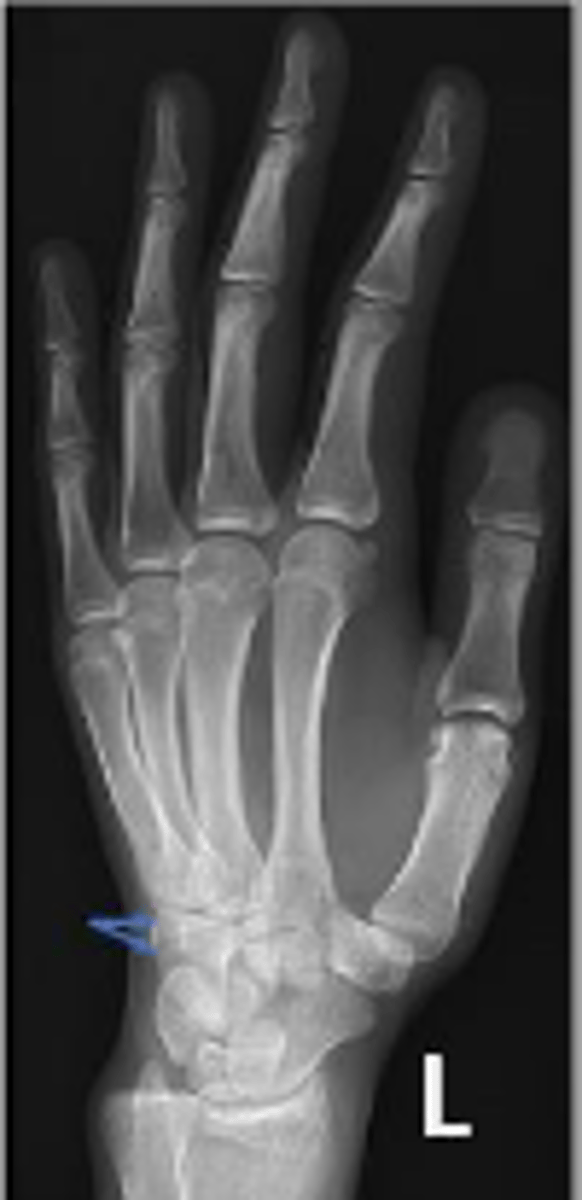

Medial oblique of the left wrist

What is the name of the radiographic view?